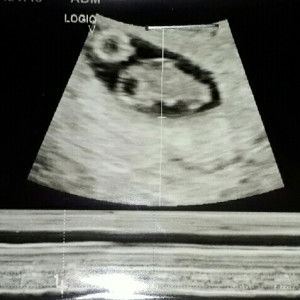

bawal po ba mga bbq,grilled food satin. korean bbq ayan or mga simpleng bbq sa kanto. pati po mg talong bawal daw po ba? I'm on my 9weeks palang po. thank you sa mag reply.

happy that I'll be having my 2nd baby